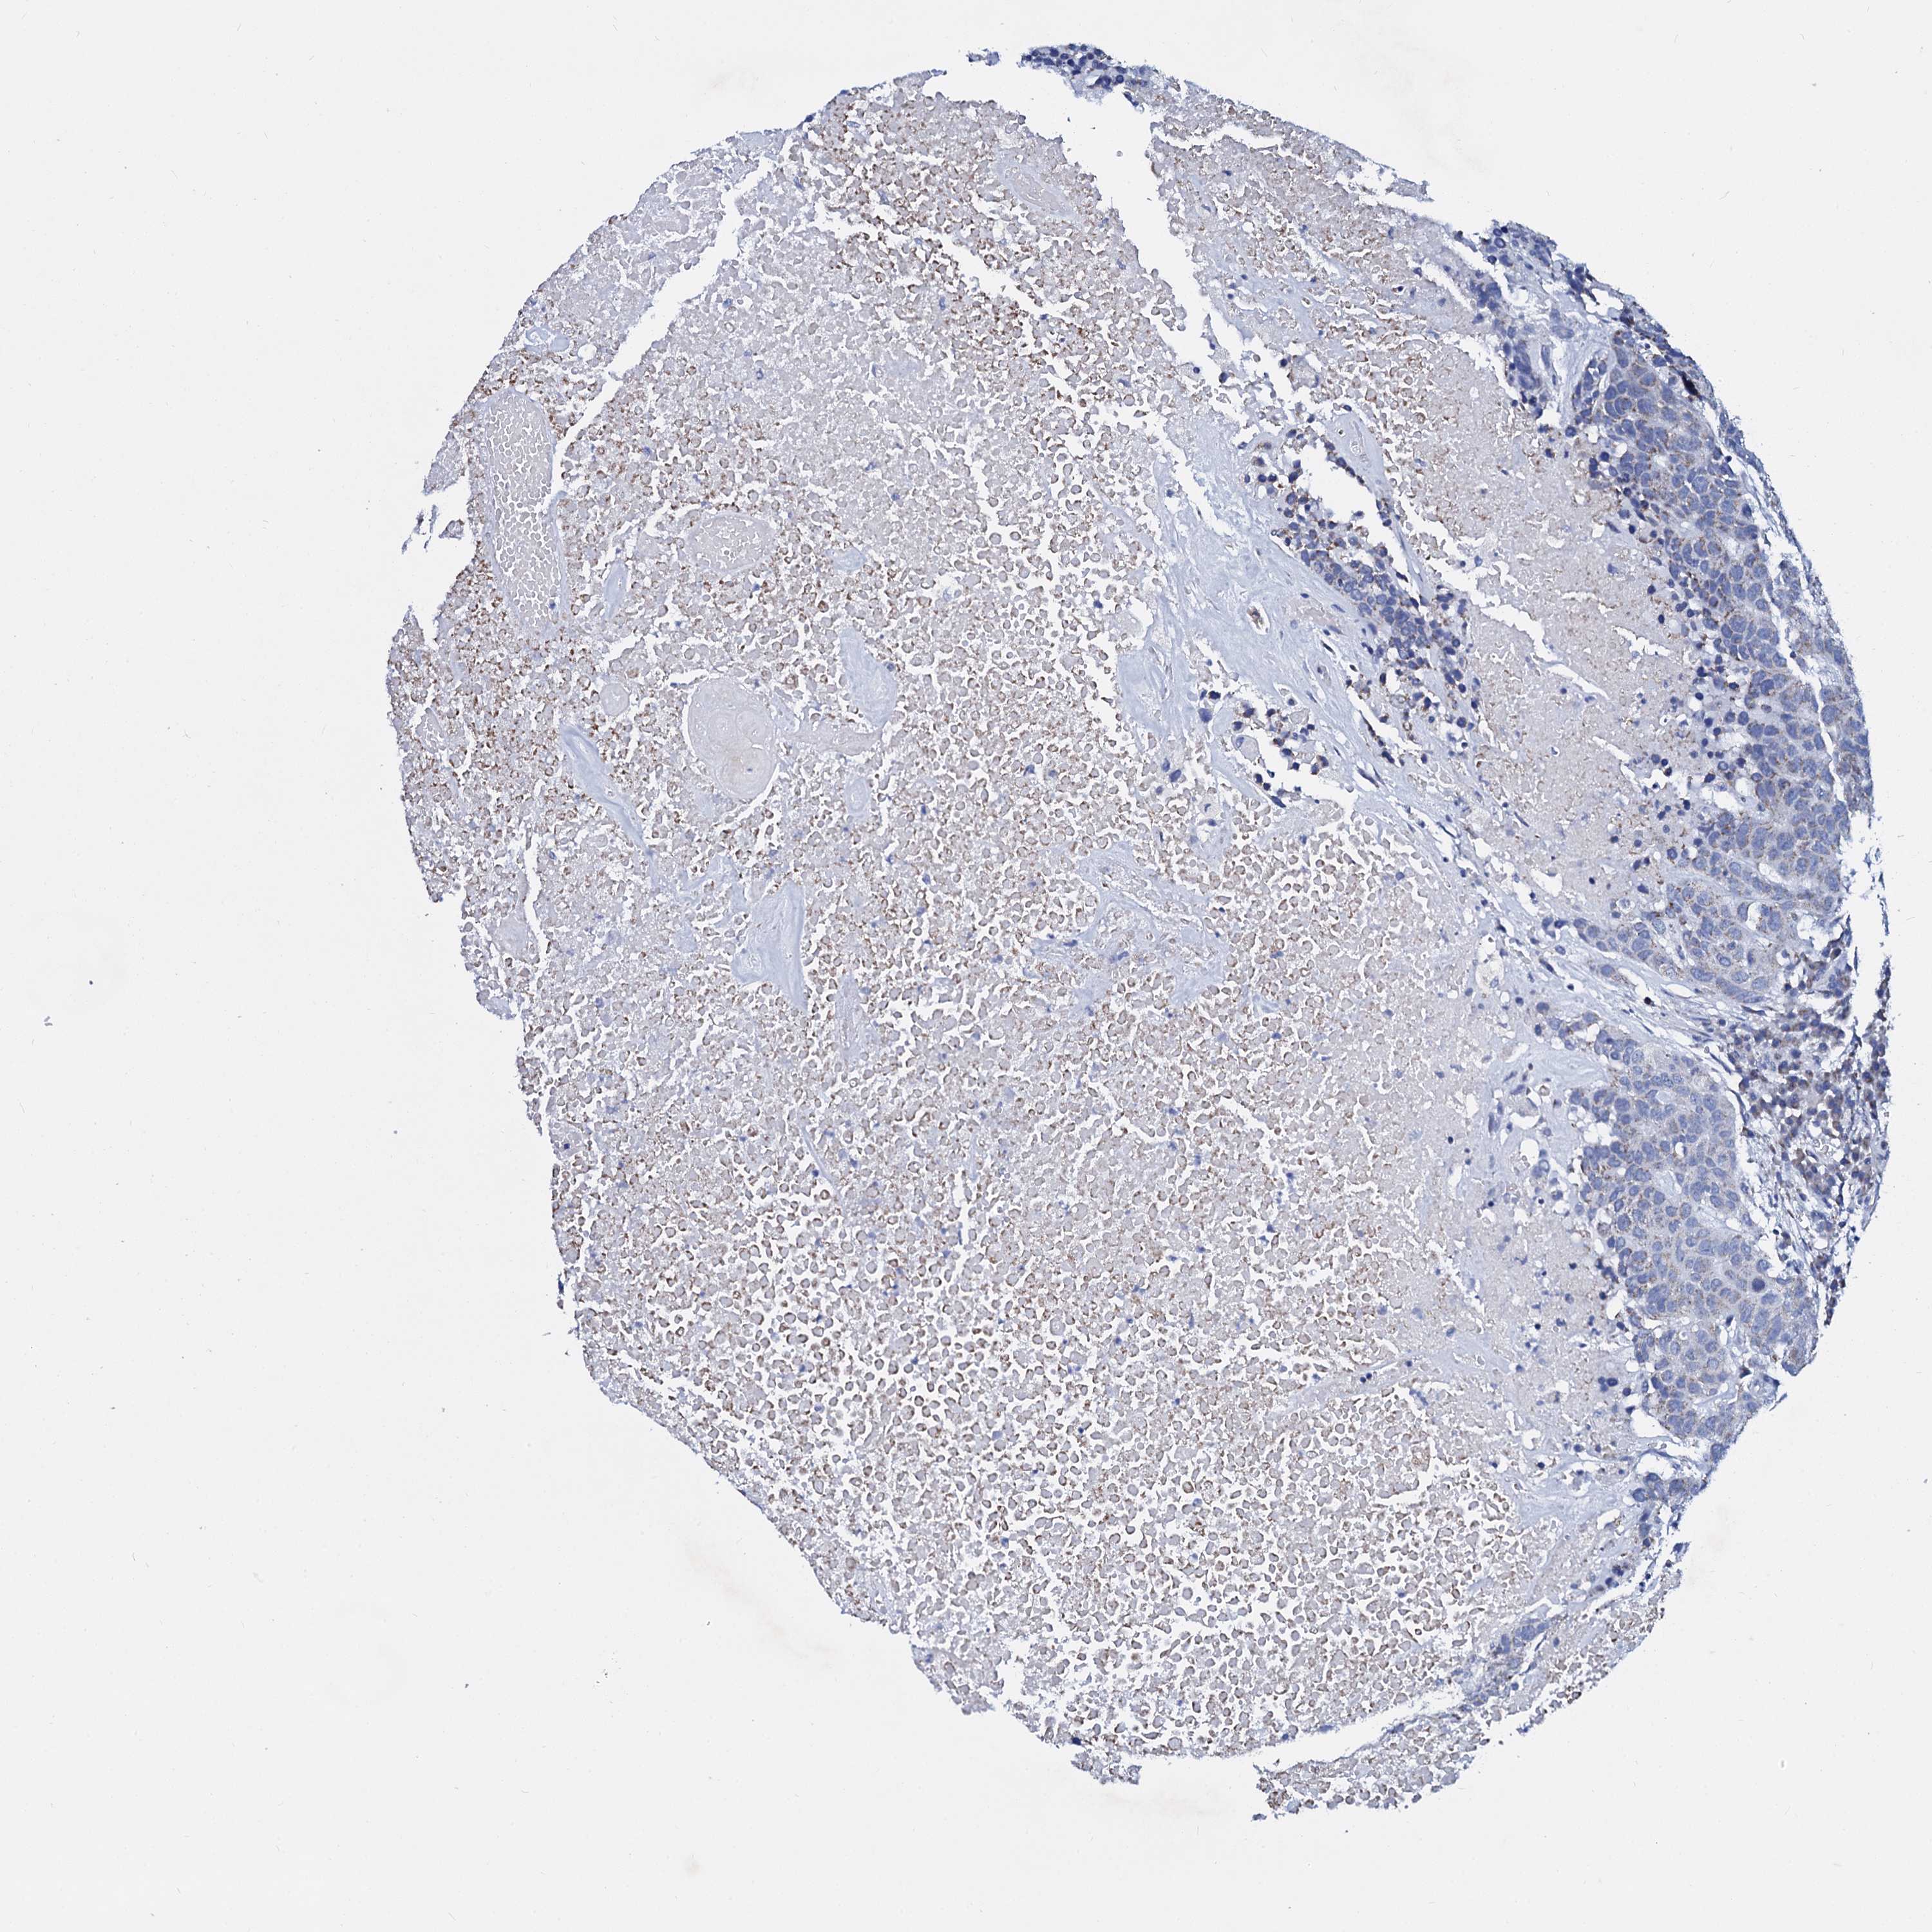

HEAD AND NECK CANCER - Protein expressioni

A mouse-over function shows sample information and annotation data. Click on an image to view it in a full screen mode. Samples can be filtered based on level of antibody staining by selecting one or several of the following categories: high, medium, low and not detected. The assay and annotation is described here.

Antibody stainingi

Antibody staining in the annotated cell types in the current human tissue is reported as not detected, low, medium, or high, based on conventional immunohistochemistry profiling in selected tissues. This score is based on the combination of the staining intensity and fraction of stained cells.

Each image is clickable and will lead to virtual microscopy that enables deeper exploration of all samples and also displays staining intensity scores, fraction scores and subcellular localization as well as patient and tissue information for each sample.

Antibody HPA038940

Staining

High

Medium

Low

Not detected

Intensity

Strong

Moderate

Weak

Negative

Quantity

>75%

75%-25%

<25%

None

Location

Nuclear

Cytoplasmic/membranous

Cytoplasmic/membranous,nuclear

Squamous cell carcinoma, NOS

Squamous cell carcinoma, metastatic, NOS